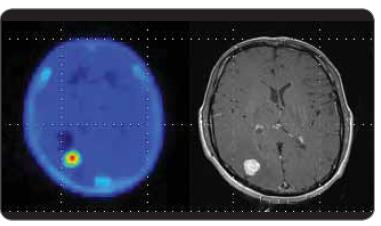

Od pozitronové emisní tomografie se v neuroonkologii požaduje odlišit benigní a maligní léze mozku, stanovit grading nádorů, určit nejvhodnější místo pro biopsii, tzv. PET-em navigovaná stereotaktická biopsie, stanovit reziduum nádoru po terapii, zjistit rekurenci nádoru, zjistit metastatické postižení mozku. Za tímto účelem je pro PET vyšetření mozku mimo 18F-fluoro-deoxy-glukózu (FDG), která tvoří základní radiofarmakum využívané pro vyšetření mozku, teoreticky možné využít množství různých neaktivních nosičů značených pozitronovými zářiči připravených v cyklotronu (18F, 11C, 13N,15O) nebo tzv. generátorových zářičů (68Ga, 82Rb). Většina non-FDG radiofarmak se však vzhledem k problémům souvisejícím s výrobou, distribucí nebo cenou využívají jenom v omezené míře, zejména v rámci výzkumných projektů. Mimo FDG se z alternativních radiofarmak v PET Centru Masarykova onkologického ústavu v Brně používají 18F- fluorothymidin a 11C-methionin. 18F-flurothymidin (FLT) je aktivně transportován TK1 v S-fázi mitotického cyklu a akumulace tohoto radiofarmaka koreluje oproti FDG s markerem proliferační aktivity Ki-67. FLT se v gliomech akumuluje cca 3krát méně než FDG, tumor/background ratio je však u FLT, vzhledem k minimální mitotické aktivitě ve zdravé mozkové tkáni, cca 3krát vyšší než u FDG. 11C-methionin ( MET) vykazuje výrazně vyšší akumulaci v lézích se zvýšenou proteosyntézou a vyšší vaskulární permeabilitou. Jeho výhodou je relativně nižší fyziologická akumulace v mozku ve srovnání s FDG. Potenciální využití tohoto radiofarmaka vidíme pro grading tumorů, zjištění relapsu po operaci nebo radioterapii, využití u stereotaktické biopsii a plánování radioterapie. Využití MET je omezené pro PET centra disponující ve své blízkosti cyklotronem, protože vzhledem ke krátkému fyzikálnímu poločasu 11C (20 min) není možné radiofarmaka značená 11C distribuovat na větší vzdálenost.